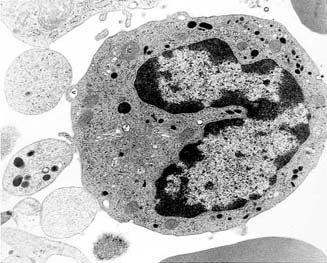

V-Macrofago

Virus MACROFAGO